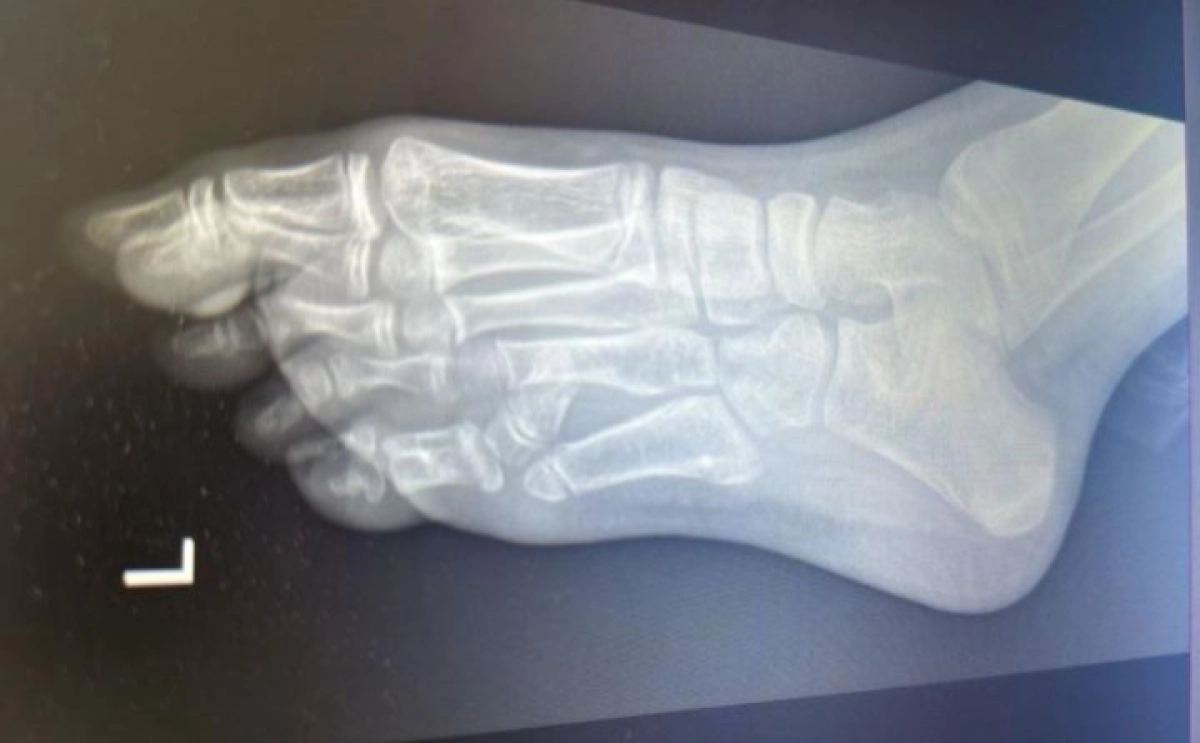

В Алматы детские хирурги провели сложную операцию по удалению лишнего пальца у 10-летней девочки, страдавшей от врожденного дефекта — шестого пальца на левой ноге, передает ИА «NewTimes.kz» со ссылкой на городское управление общественного здравоохранения.

«Это было сложное хирургическое вмешательство, которое наши травматологи-ортопеды провели совместно с коллегами из клиники высоких медицинских технологий имени Пирогова из Санкт-Петербурга. Главная сложность заключалась не только в удалении лишнего пальца, но и в дополнительной плюсневой кости, из-за которой стопа приобретала аномальную ширину. К тому же была обнаружена аномалия в расположении нервов и сосудов, что потребовало работы под микроскопом», — пояснил заведующий отделением травматологии Ерлан Садырбалин.